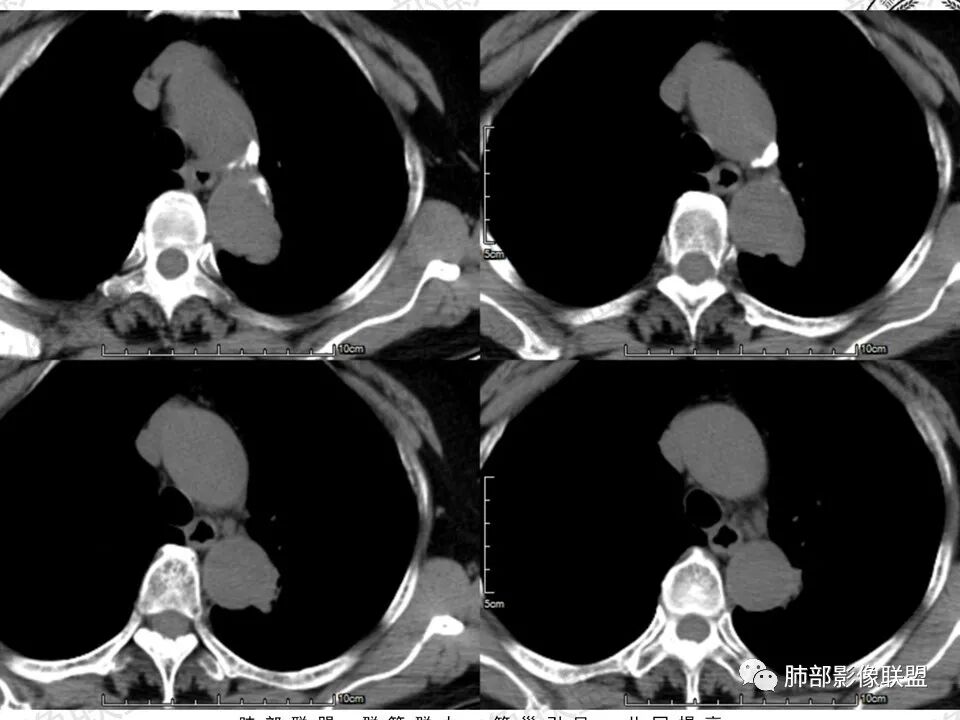

2.轴位显示主动脉弓旁依势傍行弧形高密度影,隐约见尖后段支气管进入并截止。病灶边界较清楚,见血管结构及线性影与邻近肺组织相延伸。

3.病灶渐进性显著均匀强化!动脉期未见主动脉腔异常通道。

4.冠矢状位病灶于弓上部偏后局限性“贝雷帽”状突起,提示病灶有局部膨隆特点,且病灶上份及后份饰以边缘较清楚磨玻璃影。

2.主动脉弓旁贴合弧形高密度影尤其常见于相应肺组织局限性不张和/或感染。

3.如前所述本例病灶定位于尖后段肺组织,冠矢状位病灶明显局限性膨隆感,如有老师分析时称“见较清楚磨玻璃边缘”——这应当是本例较重要诊断线索!

4.病灶显著强化是符合腺癌影像学特点的。